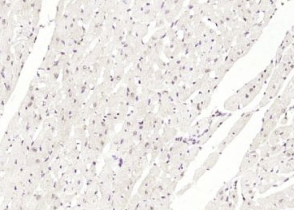

多聚甲醛固定,石蜡包埋(小鼠心脏);经柠檬酸钠缓冲液(pH6.0)煮沸15min后获得抗原;用3%过氧化氢阻断内源性过氧化物酶20分钟;阻断缓冲液(正常山羊血清)37℃30min;用(BNC1)多克隆抗体进行抗体孵育泰博体,未结合,1:400,4°C下过夜,然后根据SP试剂盒(兔子)说明和DAB染色进行操作。